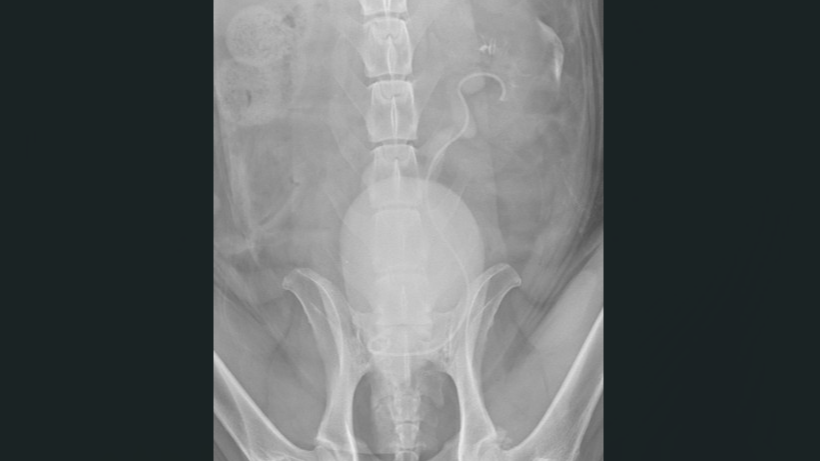

A patient was referred to Austin Veterinary Emergency & Specialty Center (AVES) for management of urinary obstruction caused by urothelial carcinoma. Initial evaluation included a positive BRAF test and imaging that revealed a prostatic mass extending into the urethra, resulting in obstruction at the left ureterovesical junction.

Nephrourology (Dr. Slead): Performed cystoscopy, identifying significant prostatic urethral thickening and tumor extension into the trigone that obscured both ureterovesical junctions, preventing retrograde stent placement. Urethral stenting was deferred, as the narrowing was partial and expected to improve with radiation therapy.

A 3.7 Fr fenestrated ureteral stent was positioned percutaneously from the renal pelvis to the bladder, successfully bypassing the tumor-associated obstruction without surgical incisions.

No intraoperative or postoperative complications occurred. Postoperative imaging confirmed ideal stent placement, and the patient demonstrated appropriate urine output.